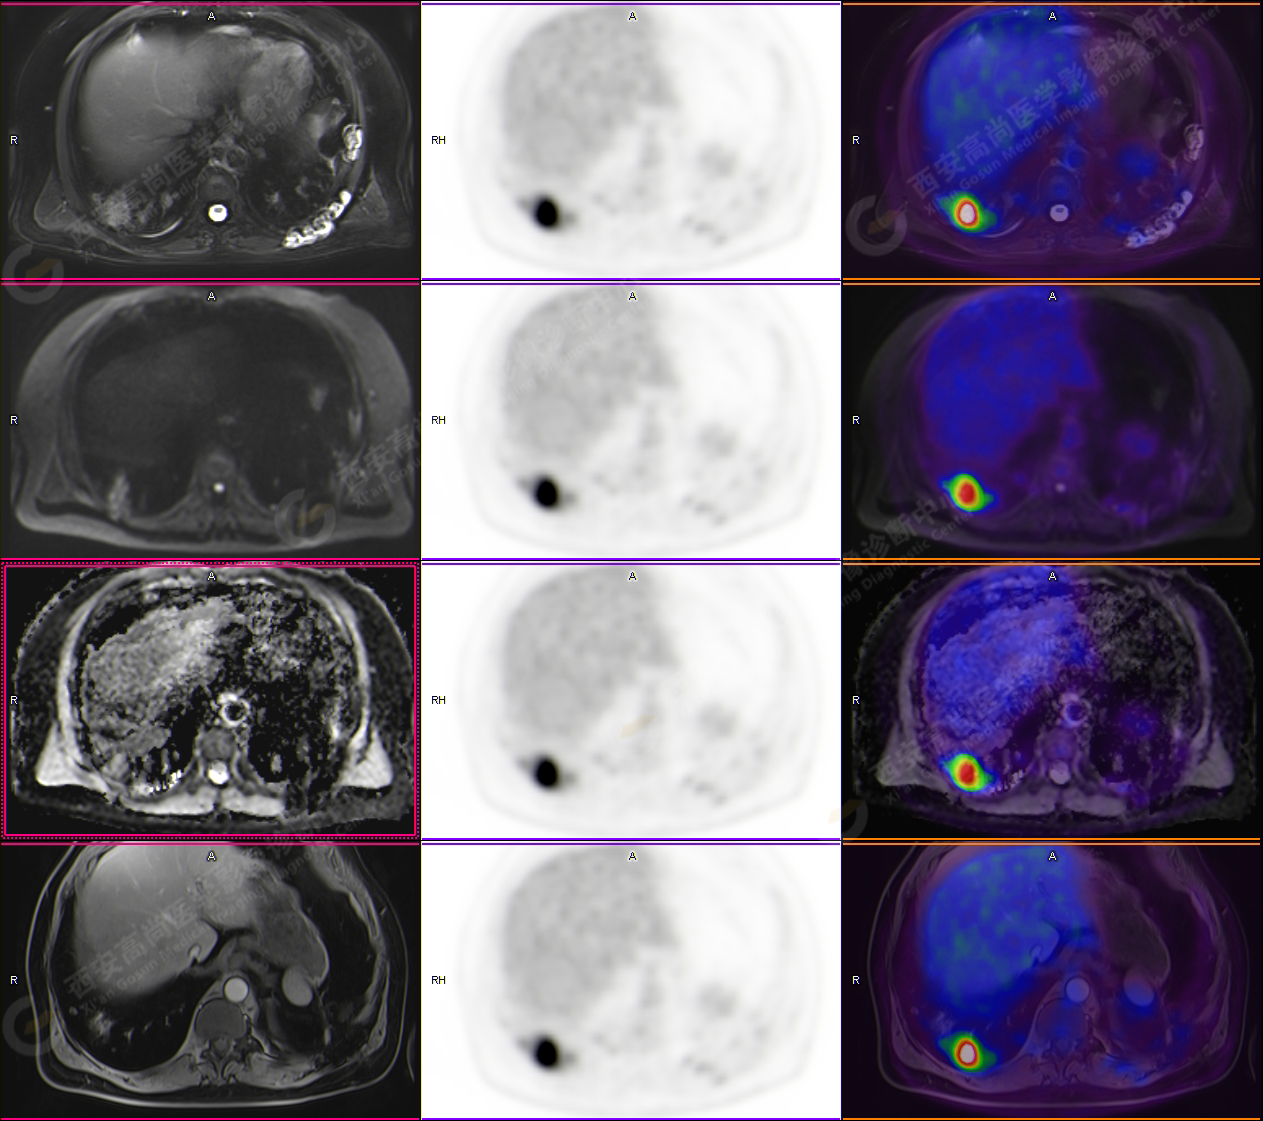

PET-MR圖像